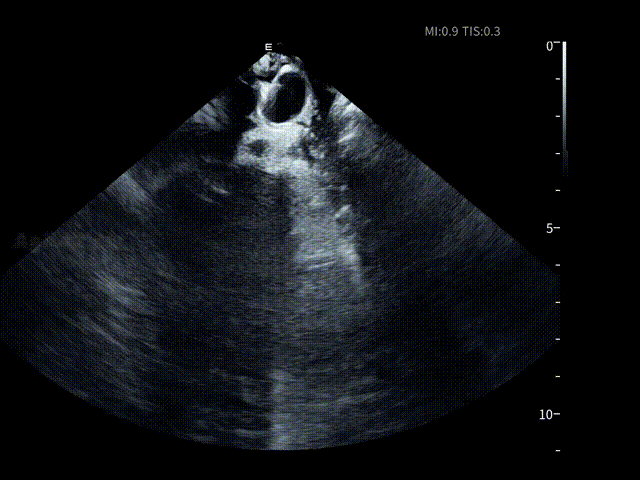

在消融手术开始前,邹操教授将ICE导管经股静脉穿刺进入右房进行术前筛查,为手术安全提供第一道影像保障。术者对左心房、左心耳及心包区域进行了系统性扫查,在导管消融前评估该患者不存在左房血栓情况,并进行术前心包监测。

AgileView™ ICE的高清实时超声成像使潜在风险在早期即可被发现与排除,让后续操作始终建立在“可视、可控”的安全基础之上,有效提升整体手术安全性。

HomeView

术前心包-有明显积液